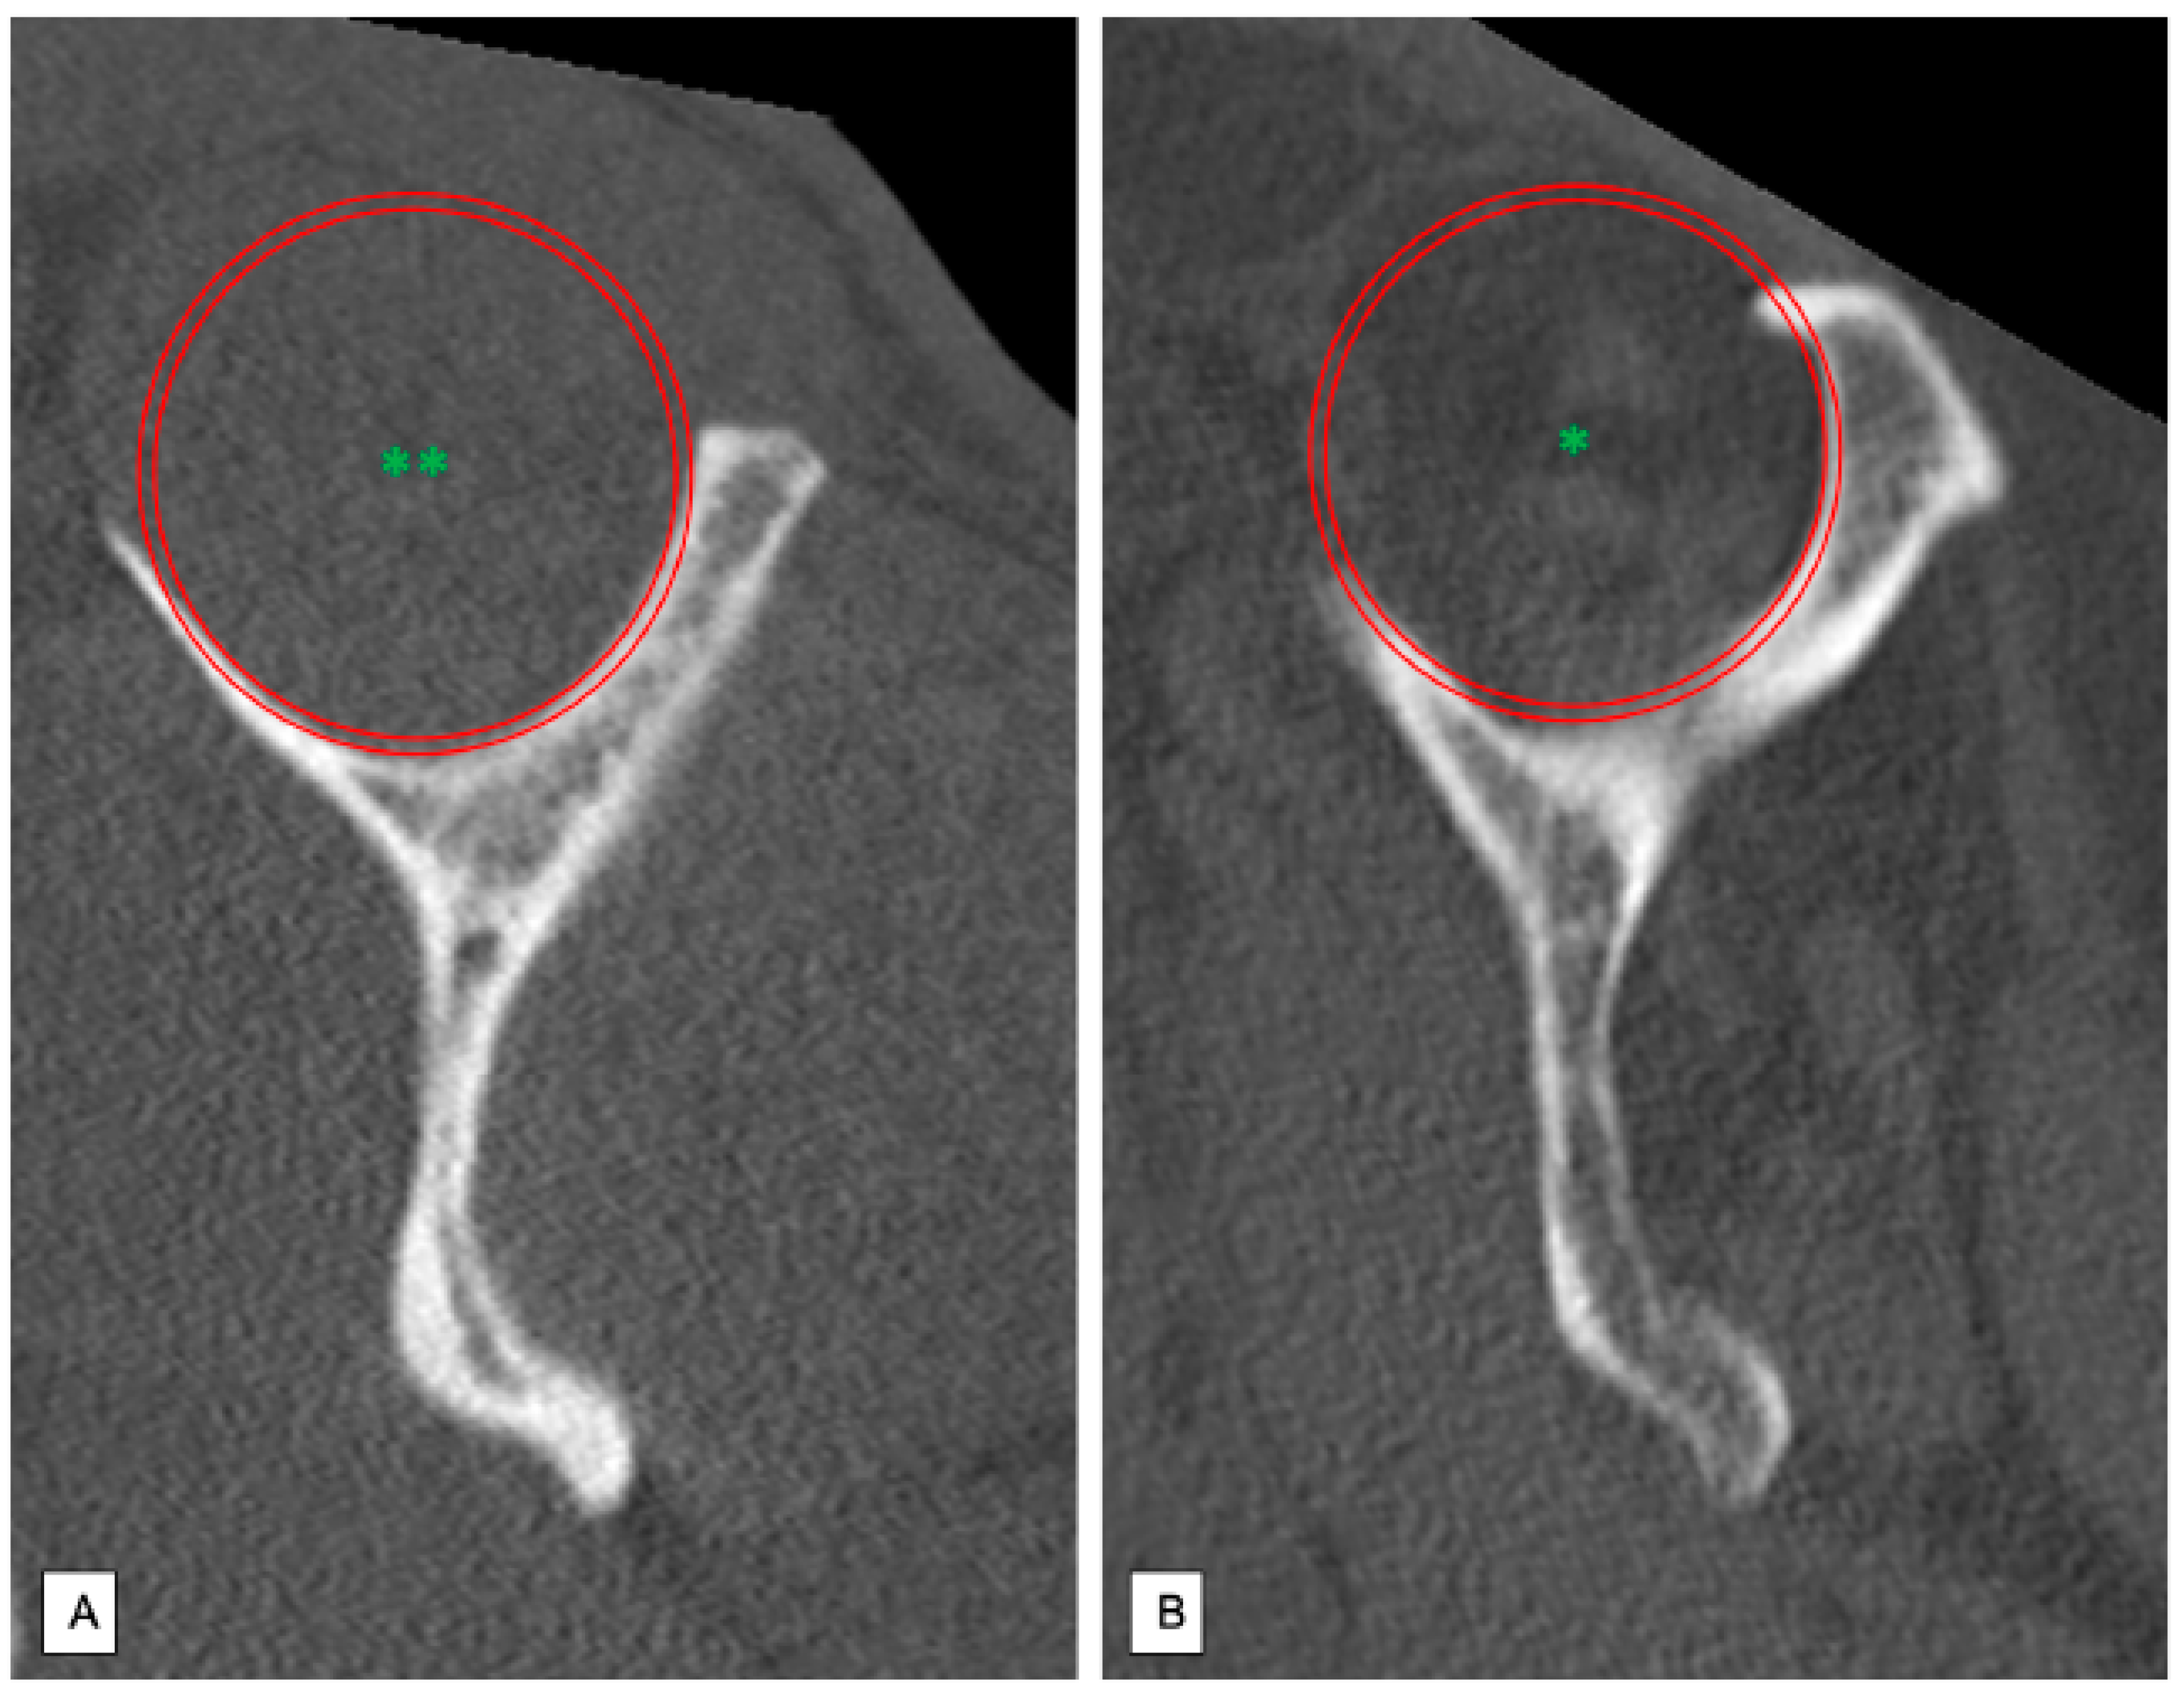

Figure 3.

Analysis of the fatty degeneration of the supraspinatus muscle using the Goutallier classification system in parasagittal slices; Red Circle: Supraspinous fossa. (A) Goutallier grade 0: No fatty degeneration of the supraspinatus muscle (**). (B) Goutallier grade 3–4: Advanced fatty infiltration of the supraspinatus muscle (*).

2.5. Classification of Fatty Degeneration of Rotator Cuff

The posterosuperior rotator cuff was evaluated using the CT-based classification system described by Goutallier [8]. Medial parasagittal slices were set in a typical “Y-shaped-position”. Thus, the supraspinous fossa could be displayed since the plane perpendicular to the scapula runs through the medial border of the coracoid process [9]. Muscular state of the supra- and infraspinatus muscle was then assessed according to Gouttallier’s classification system of fatty degeneration (grade 0 = no fatty infiltration; grade 1 = low fatty infiltration; grade 2 = less muscular fat than muscle mass; grade 3 = fatty degeneration identical with muscle mass; grade 4 = increased fatty degeneration compared to muscle mass). The patients were then divided into two groups: No or minimal fatty infiltration (Goutallier grade 0–1) (Figure 3A) and advanced fatty degeneration of the rotator cuff (Goutallier grade 2–4) (Figure 3B).